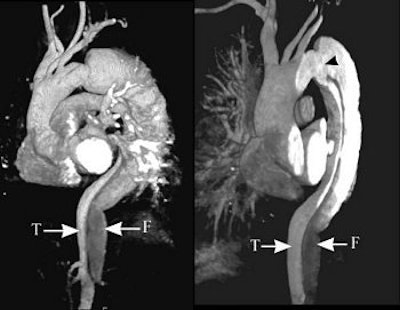

The series of images illustrate the typical manifestations of aortic dissection, including Stanford A (top image, both VR; second image, axial MPR) and Stanford B (third image, arterial phase VR, venous phase VR; fourth image, MIP and VR; fifth image, axial MPR). T = true lumen. F = false lumen. Black arrowhead = entry site. All images courtesy of Qi Liu, Ph.D.